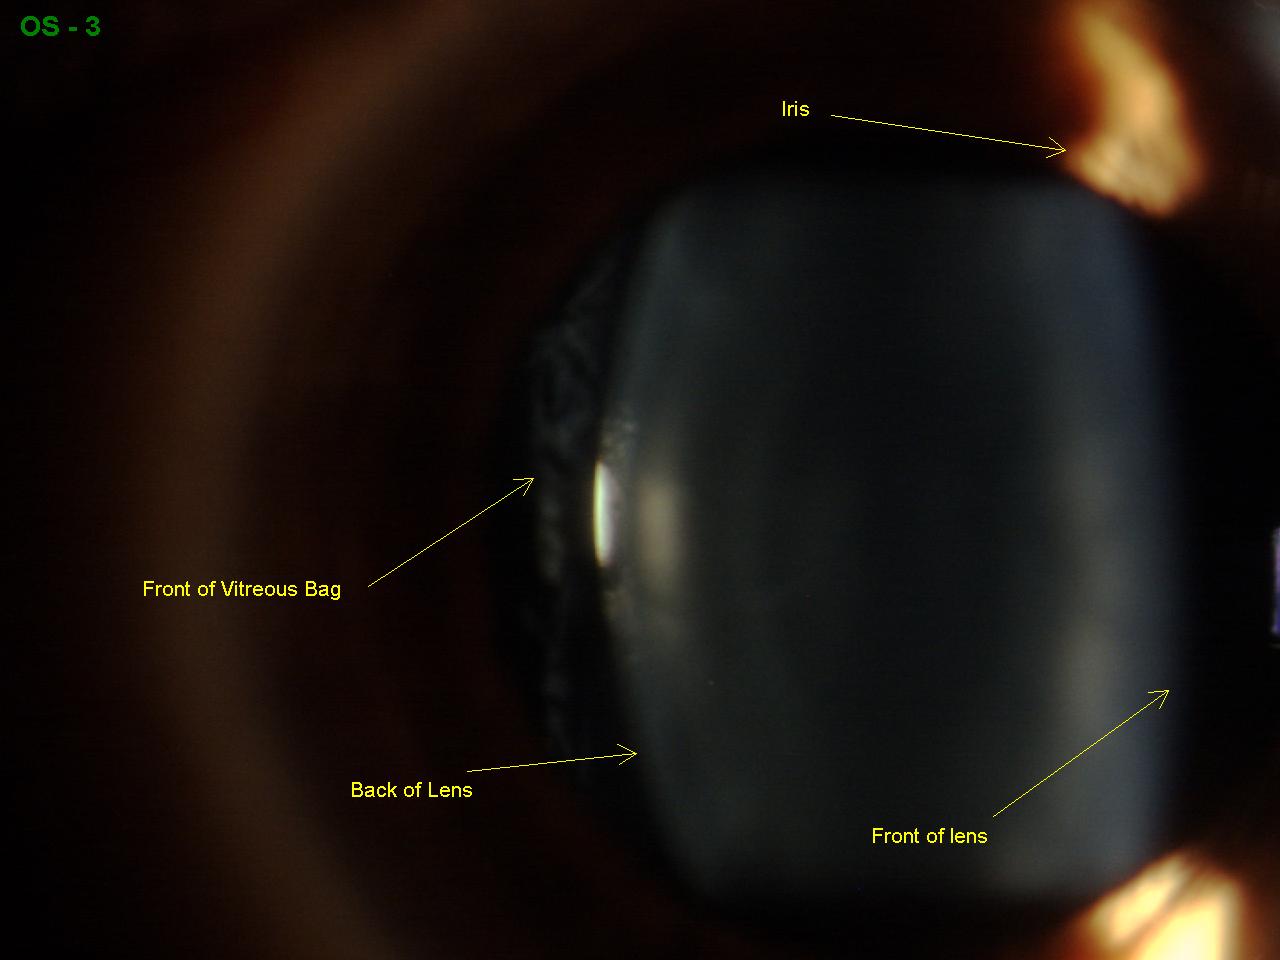

Anterior Vitreous Detachment Sonoran Desert Eye Center Dry Eye Vitreous Detachment Posterior vitreous detachment (pvd) is a condition where your vitreous comes away from the retina at the back of your eye. Vitreous detachment occurs as part of the aging process. It’s a common condition with age. Lots of people, particularly older people, get floaters and flashes. In posterior vitreous detachment (pvd), the gel that fills your eyeball separates from your. Dry Eye Vitreous Detachment.